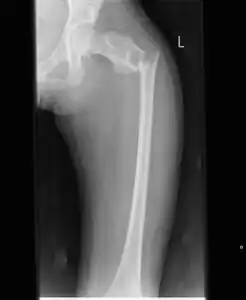

| X-ray: Simple bone cyst in left upper arm of 13 year old | |

Multloculated cavity in the long bone of the thigh, near the hip. -

Break through simple bone cyst in the long bone of the thigh, near the hip.